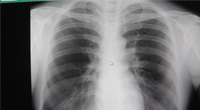

それぞれの検診内容によって様々です。大腸がんでは便潜血検査や大腸内視鏡検査。肺がんでは胸部X線など。また、採血により腫瘍マーカーの検査が可能です。